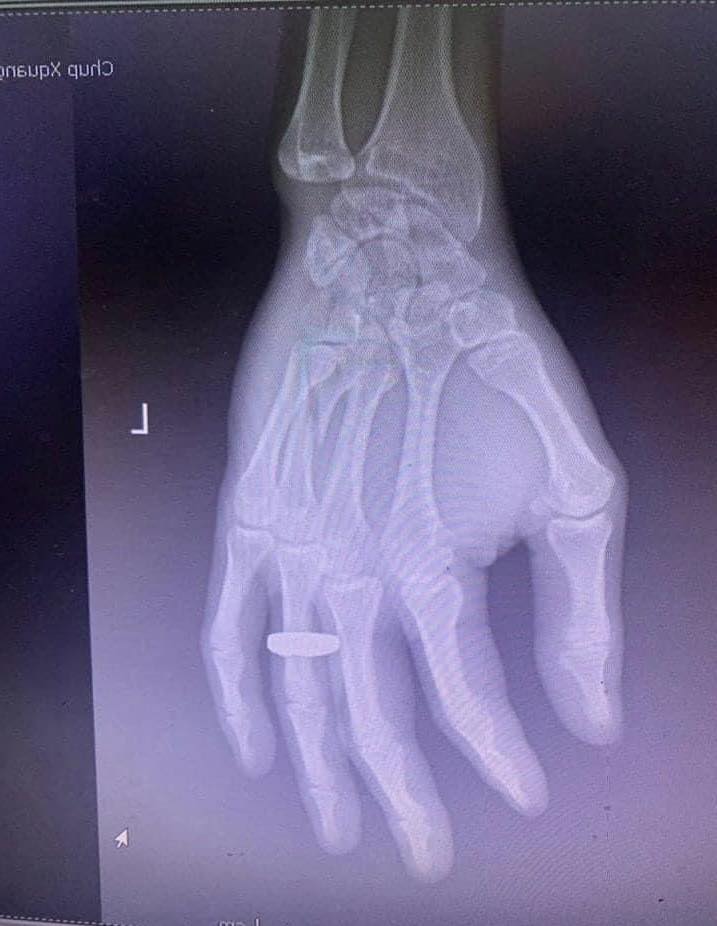

31/10/2022 17:28Chê vé đắt và đòi xuống xe, hành khách bị nhân viên nhà xe đánh gãy tay

Ngày 31/10, trên MXH bất ngờ xuất hiện đoạn clip ghi lại cảnh một nhân viên nhà xe tuyến xe khách Hà Nội - Quang Ninh đang ghì chặt hành khách xuống ghế và liên tục dùng tay để đánh vào đầu nam hành khách.

Cụ thể theo nội dung đoạn clip, một nam hành khách lên xe từ Hà Nội đi Móng Cái , Quảng Ninh và phàn nàn rằng vé xe bị đắt. Ngay lập tức một nhân viên nhà xe đã tức giận và đánh đấm liên tục nam hành khách trên. Sự việc chỉ dừng lại khi rất nhiều người trên xe khách lên tiếng. Sau đó, nam hành khách tiếp tục bị nhân viên nhà xe đuổi xuống xe khi chiếc xe khách mới đi đến Bắc Ninh.